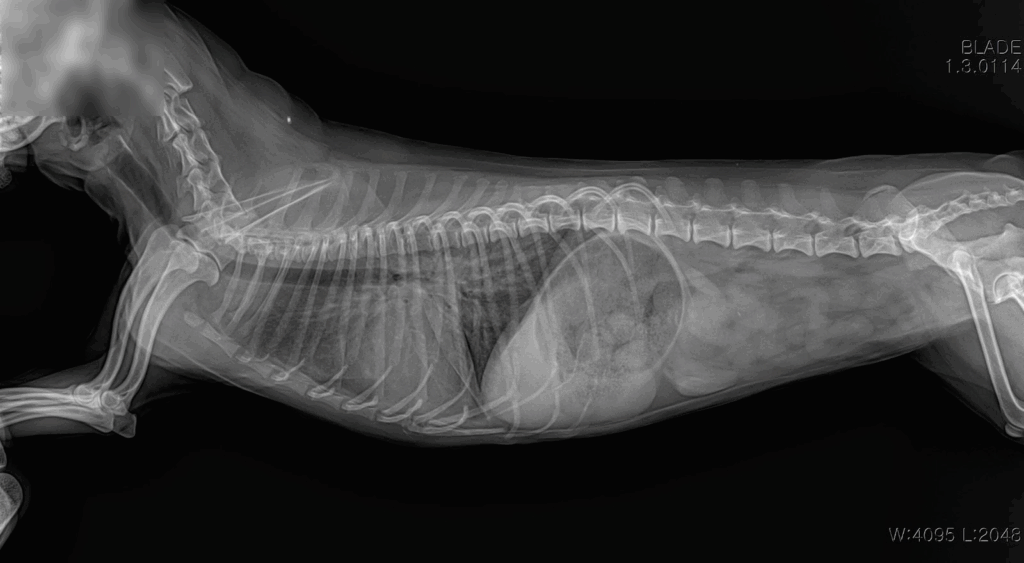

📌 흉부 X-ray

X-ray 촬영은 심장의 크기와 모양, 그리고 폐에 물이 차 있는지 여부를 확인하는 데 사용됩니다. 이를 통해 심장비대나 폐수종 같은 합병증 여부를 빠르게 파악할 수 있습니다.

내원 당시 흉부 방사선 사진: 심장 비대 및 폐수종 확인

검사 결과 심부전 소견이 확인되었고, 이에 따라 약물 관리를 통한 환축 안정화를 목표로 치료를 시작했습니다.

흉부 방사선 촬영에서도 폐수종 소견이 호전되어, 환축이 안정된 상태로 생활할 수 있게 되었습니다.